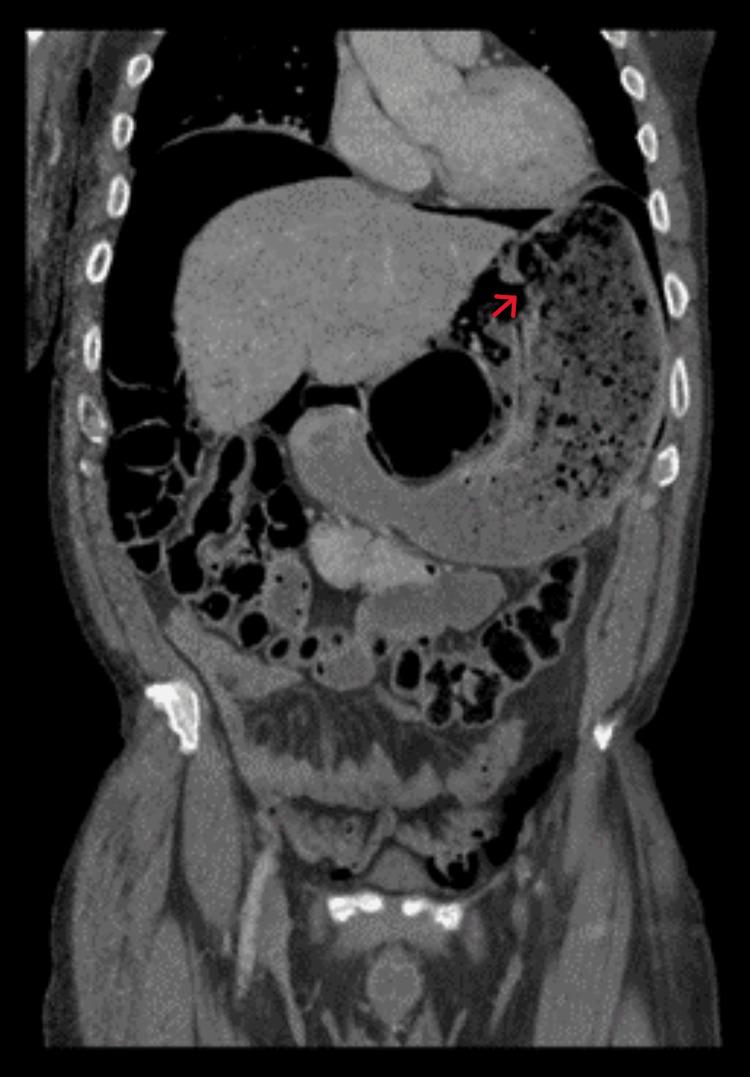

A gastric rupture resulting from abdominal trauma is a rare occurrence with a frequency of less than 2% of blunt abdominal injuries. Furthermore, gastric perforation secondary to the Heimlich maneuver is even rarer, with only a handful of cases reported in the literature. Here, we present a case of isolated gastric rupture following a successful Heimlich maneuver. Laparotomy revealed a large perforation along the lesser curvature of the stomach. The perforation was repaired by primary closure and reinforced with omental patching.

腹部创伤导致的胃破裂是一种罕见的情况,在钝性腹部损伤中发生率不到2%。此外,海姆立克急救法继发的胃穿孔更为罕见,文献中仅报道了少数病例。在此,我们报告一例成功实施海姆立克急救法后发生孤立性胃破裂的病例。剖腹探查发现胃小弯处有一个大穿孔。穿孔通过一期缝合修复,并用网膜补片加固。